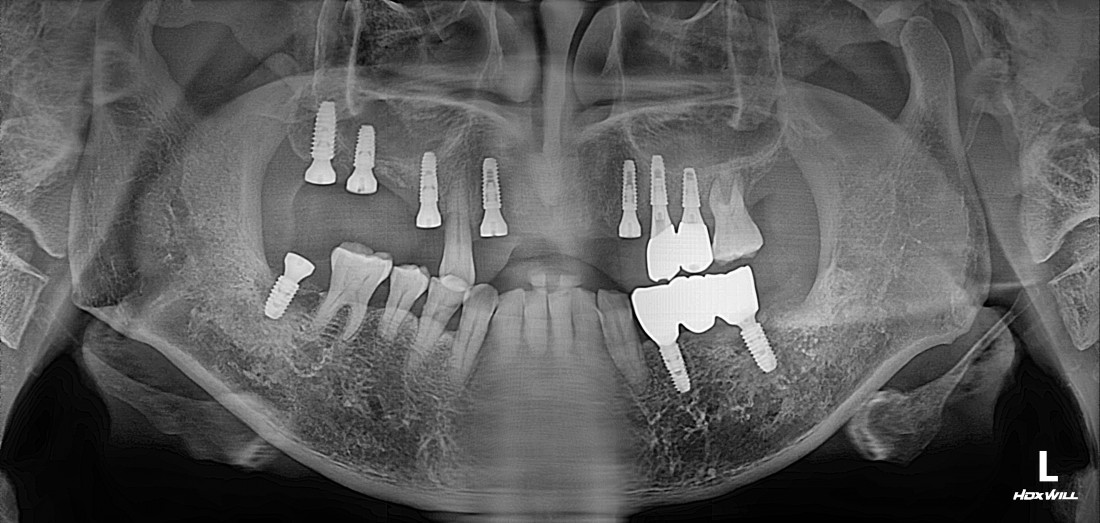

한 번에 8개 이상 식립이 가능한

광주 앞니 임플란트 치과의

디지털 가이드 임플란트로

아프지 않은 임플란트!

디지털 가이드 임플란트는

잇몸을 무절개 (최소절개)로 하여

임플란트 식립이 가능합니다.

그렇기 때문에 수술시간이 짧으며,

붓기 / 출혈 / 통증이 적어서

회복도 매우 빠르다는 큰 장점이 있습니다.

광주 앞니 임플란트치과의

아프지 않은 / 예쁜 / 잘 씹어지는

앞니 임플란트로

새로운 미소를 되찾아보세요!